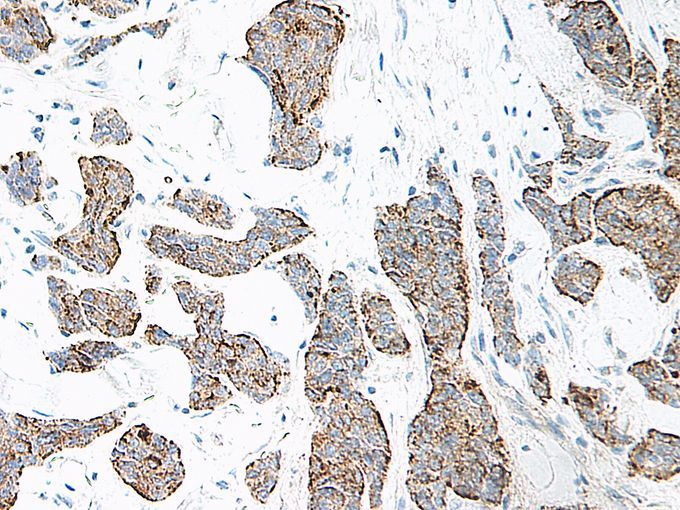

- IL17 antibody

Supportive validation

- GeneTex (provider)

- IHC-P analysis of human breast invasive ductal carcinoma using IL17 antibody. An HRP-labeled polymer detection system was used with a DAB chromogen. Heat induced antigen retrieval with a pH 6.0 sodium citrate buffer is recommended.